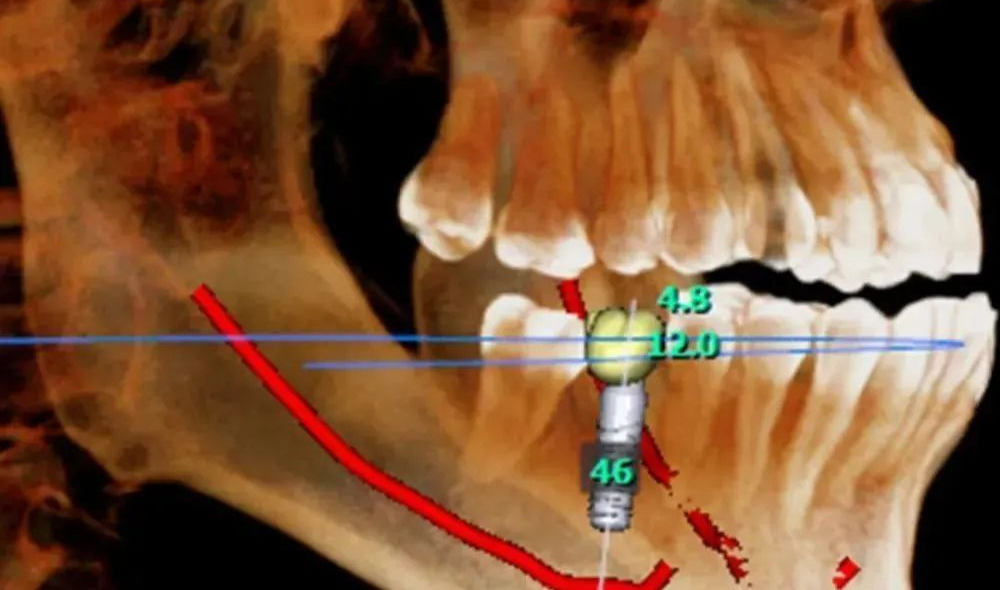

(7)种植牙。CBCT设备可以辅助种植手术的设计,制作种植导板,精确控制种植体的位置、方向、长度、直径等,最大程度利用患者现存骨量,优化种植体的位置,避免在种植手术过程中不慎破坏神经、鼻窦等解剖结构而导致颜面神经麻痹、鼻窦炎等并发症。使种植手术更安全便捷,确保手术及后期修复的成功。